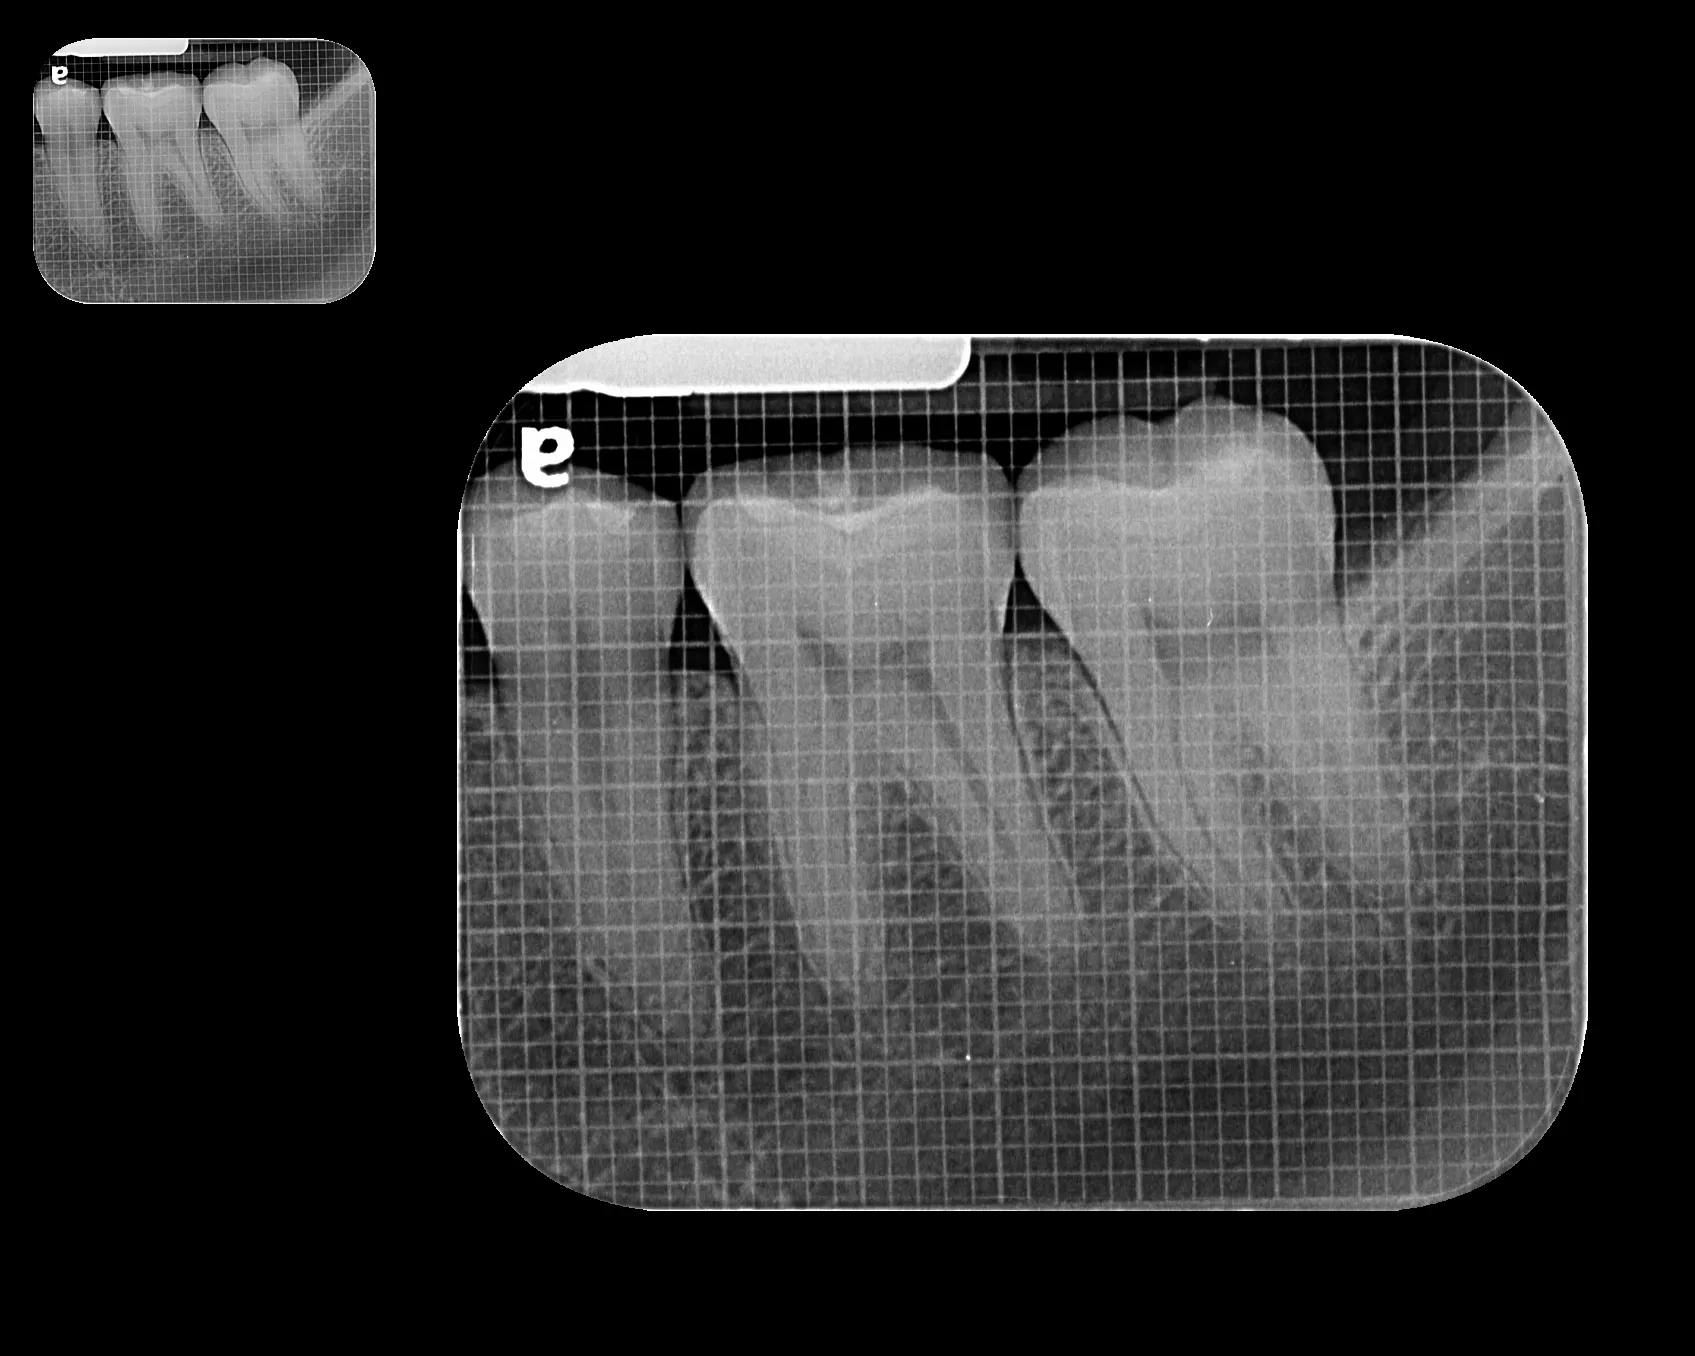

Radiografía Intraoral

La radiografía intraoral permite observar con gran detalle los dientes y las estructuras que los rodean. Es una herramienta fundamental para detectar caries, infecciones, fracturas, alteraciones en la raíz dental o en el hueso de soporte.